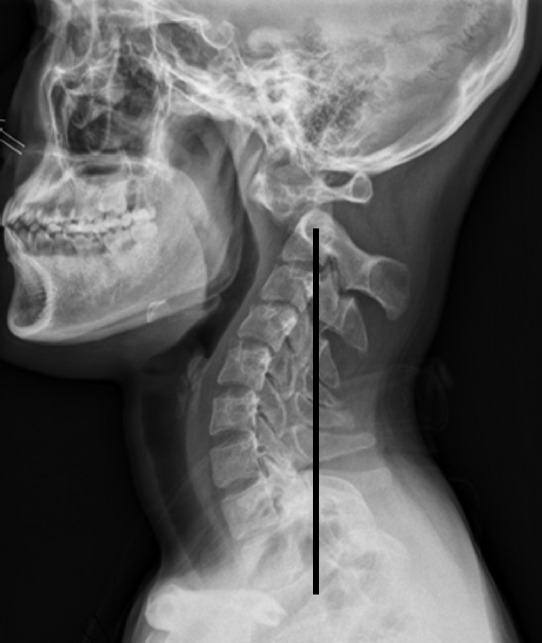

Methods: A retrospective analysis was performed on 28 patients who underwent craniocervical realignment between 2014 and 2022 for CVJ kyphosis with accompanying negative sagittal imbalance. Clinical outcomes were evaluated using the Neck Disability Index (NDI), visual analogue scale for neck pain, and the Japanese Orthopaedic Association (JOA) score. Radiographic parameters included the C0-2 angle and the C2-7 sagittal vertical axis (SVA). Favorable outcomes were defined as an improvement of more than 20 points in the NDI and a JOA recovery rate exceeding 50%. Multiple linear regression and receiver operating characteristic (ROC) curve analyses were conducted to identify independent predictors and to determine optimal threshold values.

Results: Significant improvements in both clinical outcomes and radiographic alignment were observed in association with craniocervical realignment surgery. Patients who achieved favorable outcomes exhibited greater postoperative changes in the C0-2 angle and the C2-7 SVA. Multivariate analysis identified changesm in the C0-2 angle (p=0.019) and C2-7 SVA (p=0.010) as independent predictors of NDI improvement, while age (p=0.033) and C2-7 SVA change (p=0.037) were independently associated with the JOA recovery rate. ROC curve analysis determined optimal cutoff values of ≥10.65° for C0-2 angle change and ≥19.2 mm for C2-7 SVA change, with corresponding area under the curve values of 0.872 and 0.802, respectively.